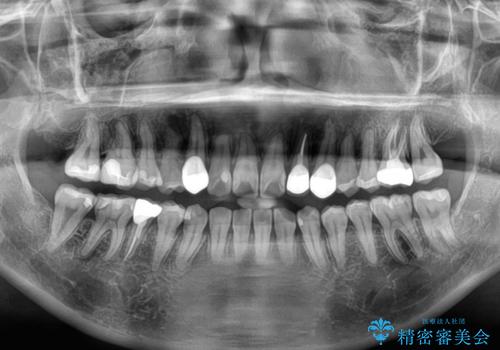

- 上下の歯が非接触であり、八重歯やむし歯を気にして来院された患者様です。

下顎骨の左右偏位はあるものの、上顎骨幅が相対的に狭い状態であったので、奥歯の咬み合わせが非常に乱れていました。

急速拡大装置により上顎骨幅を側方に拡大し、それを利用して八重歯を歯列に納めることにしました。

矯正治療後は全顎的にむし歯が多いため、セラミッククラウンやインレーにより補綴治療を行うこととしました。

急速拡大が奏効し、非抜歯矯正にて八重歯を解決することができました。